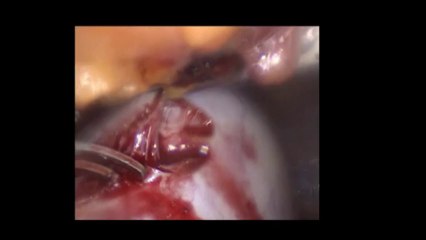

Diagnostik laparoskopi - Prof. Dr. Aydan Biri